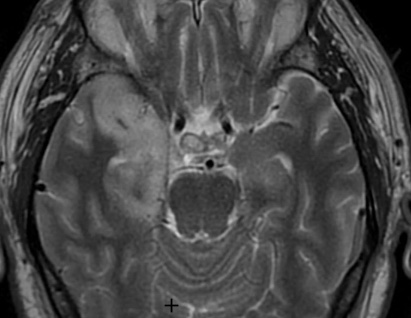

Encéphalite Varicelleuse (VZV)

- Réactivation de varicelle latente dans le ganglion dorsal / nerf cranien → Zona

- Chez les immunosupprimés (HIV) ++

- Fait des vasculites des artères intra-cranienens